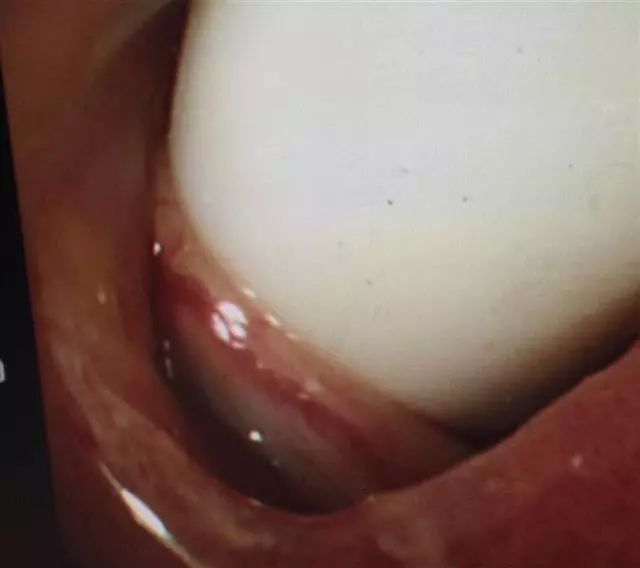

当天下午,她从应城当地医院转到了武汉大学中南医院。该院消化内科副主任医师齐健检查发现,牙刷柄已经把患者的十二指肠球部顶破了一个洞,其十二指肠降部也被牙刷头戳伤形成溃疡。

据医生分析,正是由于牙刷柄紧紧地卡在穿孔的洞口,才使患者吞下牙刷后的十多天吃的食物和水没有进入腹膜腔,如果再拖延手术,随时可能有生命危险。

除夕晚上,该院胃肠外科蔡小鹏医生为袁女士进行了急诊手术,完整取出了一把15厘米的牙刷。经过一段时间康复治疗,13日,袁女士康复出院。